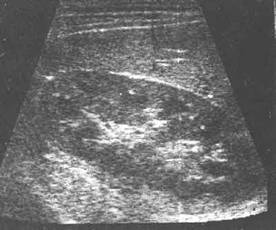

肾脏纵切超声显像图

脂肪囊:绕于肾周强回声光带。一般厚约0.5-1cm。

肾实质:分布均匀细小光点回声,皮质回声较强,髓质回声较弱。

集合系统:位于肾脏中央带状强回声,边缘不规则,分布不很均匀。